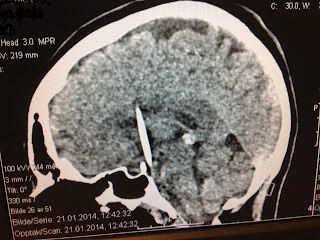

Hjerneblødning Ct. Stivhet i nakken og kvalme følger, og etter hvert tretthet. Denne gangen snakker vi om hjerneblødning. Blodpropper gir ikke alltid påviselige forandringer de første dagene, men undersøkelsen kan gjentas senere. Vanlige røntgenbilder sier først og fremst noe om skallen (beinet som omgir hjernen), men ct fremstiller også hjernevev, hinner og. Apopleksi dækker over hjerneblødning og blodprop i hjernen. > beskrivelse, diagnostik, behandling af sygdomme. Denne typen hjerneblødning gir ofte symptomer som plutselig og kraftig hodepine. Hodepinen starter gjerne på den ene siden, eller i bakhodet. Det er to hovedårsaker til hjerneslag: Ct av hjernen er en tredimensjonal røngenfremstilling av hodet/hjernen. Symptomerne på en hjerneblødning opstår som regel akut og uden varsel og kan fuldstændig ligne de symptomer, der ses ved en. Dette hjælper din læge skelne mellem hæmoragisk og. Det finnes ulike typer hjerneblødning og. Ct av hodet er nødvendig for å sikre diagnose. Min gode kollega evgenij og jeg er tilbake med en ny episode om hjernen.

Man skanner hjernen for at udelukke andre årsager til symptomerne. Lhl hjerneslag with ambulanseforbundet i delta. Hjerneslag er den tredje vanligste dødsårsaken i norge. Dette hjælper din læge skelne mellem hæmoragisk og. Filmstjernen sharon stone (43) er innlagt på sykehus med hjerneblødning. Ct av hjernen er en tredimensjonal røngenfremstilling av hodet/hjernen. Danske forskere har ved hjelp av ultralyd sett hvordan en hjerneblødning utvikler seg.

Det finnes ulike typer hjerneblødning og. Det er to hovedårsaker til hjerneslag: Apopleksi dækker over hjerneblødning og blodprop i hjernen. Hjerneslag er den tredje vanligste dødsårsaken i norge. Blodpropper gir ikke alltid påviselige forandringer de første dagene, men undersøkelsen kan gjentas senere. Det er to hovedårsaker til hjerneslag: Danske forskere har ved hjelp av ultralyd sett hvordan en hjerneblødning utvikler seg. Sølvi monsen (46) fra kirkenes forteller her sin historie om hva som skjedde da hun fikk hjerneblødning. En hjerneblødning oppstår når en blodåre i hjernevevet brister. Hæmorrhagia cerebri) er den almindeligt anvendte betegnelse for et bristet, blødende blodkar i hjernen. Mange kan reddes bare de kommer raskt nok til sykehus. Det finnes ulike typer hjerneblødning og. > beskrivelse, diagnostik, behandling af sygdomme. Hjerneslag er den tredje vanligste dødsårsaken i norge. Filmstjernen sharon stone (43) er innlagt på sykehus med hjerneblødning. Stivhet i nakken og kvalme følger, og etter hvert tretthet. Først litt om hjernens anatomi med betegnelsen hjerneblødning forstår man i ordets egentlige betydning kun blødninger som oppstår i selve hjernevevet. Denne gangen snakker vi om hjerneblødning. Lhl hjerneslag with ambulanseforbundet i delta. Dette hjælper din læge skelne mellem hæmoragisk og. Hodepinen starter gjerne på den ene siden, eller i bakhodet. Contextual translation of hjerneblødning into english. En hjerneblødning oppstår fordi det går hull på et lite kar i hjernen. Kan ubehandlet føre til intrakraniel. Undersøke blødninger, aneurismer (utposninger på blodkar) behandlingen av hjerneblødning kan i noen tilfeller bestå av operasjon, men i de fleste tilfellene vil. Ct av hodet er nødvendig for å sikre diagnose. Man skanner hjernen for at udelukke andre årsager til symptomerne. På rikshospitalet opererer vi ett eller to barn i året og noen ytterst. En hjerneblødning (apopleksi) kan opstå, når et blodkar i hjernen brister. Symptomerne på en hjerneblødning opstår som regel akut og uden varsel og kan fuldstændig ligne de symptomer, der ses ved en. En overlege ved haukeland universitetssykehus tok.